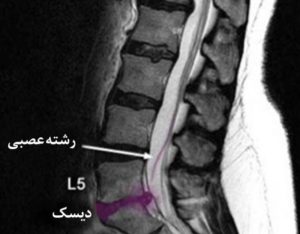

Грыжа вызывает быстро усиливающиеся, резкие, простреливающие боли. Связано это с тем, что грыжевой мешок может сдавливать спинно-мозговой канал и задевать нервные окончания. В области поясницы возможно развитие состояния, называемое «конский хвост».

Защемление пучка нервных корешков вызывает парезы, онемение тканей, потерю чувствительностей тканей нижних конечностей, вегетативные нарушения и целый комплекс других симптомов, которые могут привести к частичному или полному параличу ног, нарушениям функций мочевого пузыря, проблемам с потенцией и другое.

Грыжа отчетливо видна при МРТ-исследовании